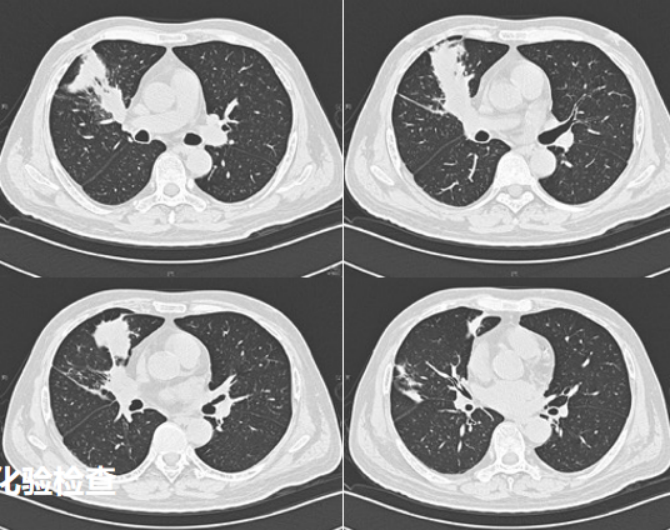

病例7男性,52岁。主诉:反复发热2个月。体温最高39℃。外院行胸部CT考虑“肺部感染”,多次查真菌G试验/GM试验均阴性,结核T细胞检测阴性。患者于外院共3次行电子气管镜检查。BALF-mNGS显示为轻链球菌、咽峡炎链球菌、人类疱疹病毒5型。反复抗感染治疗无效。既往史:2021年2月确诊为急性髓系白血病,行化疗4次,2021年4月11日行非血缘脐带血干细胞移植治疗。3个月前有可疑结核接触史。吸烟30余年,约20支/日。2021年6月17日胸部CT示右肺上叶前段、中叶、后叶均可见病变(图10)。组织病理学检查发现大量真菌菌丝及孢子(图11)PAS及GMS染色均呈阳性,结合上述结果可以明确诊断为毛霉感染,后续mNGS进一步印证了该诊断。支气管镜下2次冷冻活检取脓栓(图12)。予右肺上叶前段支气管共灌注两性霉素B 5次,每次15 mg。右肺下叶内基底段共灌注两性霉素B 5次,每次10 mg。经过4周的治疗,患者肺部病变消失(图13)。半年后再次复查支气管镜,镜下表现正常(图14)

图片

10  病例7治疗前胸部CT

13  病例7治疗前后胸部CT对比